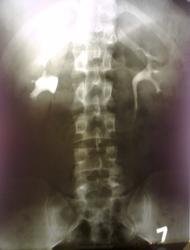

Молодой человек с субфебрильной температурой.Незначительные воспалительные изменения в моче, крови.

У меня вопрос-можно ли назвать это краевым псоас-симптомом или это высокое отхождение правого мочеточника+пиелоэктазия , либо все вместе?

Псоас-симптом справа, пиелокаликоэктазия справа, нарушение цистоидной функции правого мочеточника. Опытные коллеги, поправьте, если что )

На мой взгляд, типаж "псоас - симптома", даже если "там" есть и ещё кроме....

Виктор Григорьевич, это солдат срочной службы с жалобами.Местный.Болит у него .На УЗИ нашли пиелоэктазию-наши в таких случаях сразу внутривенную урографию назначают, потом ВВК на предмет годности к военной службе , а мне не хочется перед ясным ликом Главного рентгенолога выглядеть не очень.

В принципе, есть, чему болеть. Вполне вероятен вазо-ренальный конфликт с нарушением оттока из лоханки. В результате хронический пиелонефрит. Красивый psoas-симптом

.Стриктура мочеточника в ЛМС-основное, отсюда-пиелоэктазия.

Здесь необходимости в дополнительных проекциях нет.Всё ясно и так.Достаточно оценить первый снимок: лоханка переполнена, а заполнение мочеточника явно отстаёт.

как свидетельствуют классики "псоас - симптом" свидетельствует только о гипотонии лоханки... и не более.